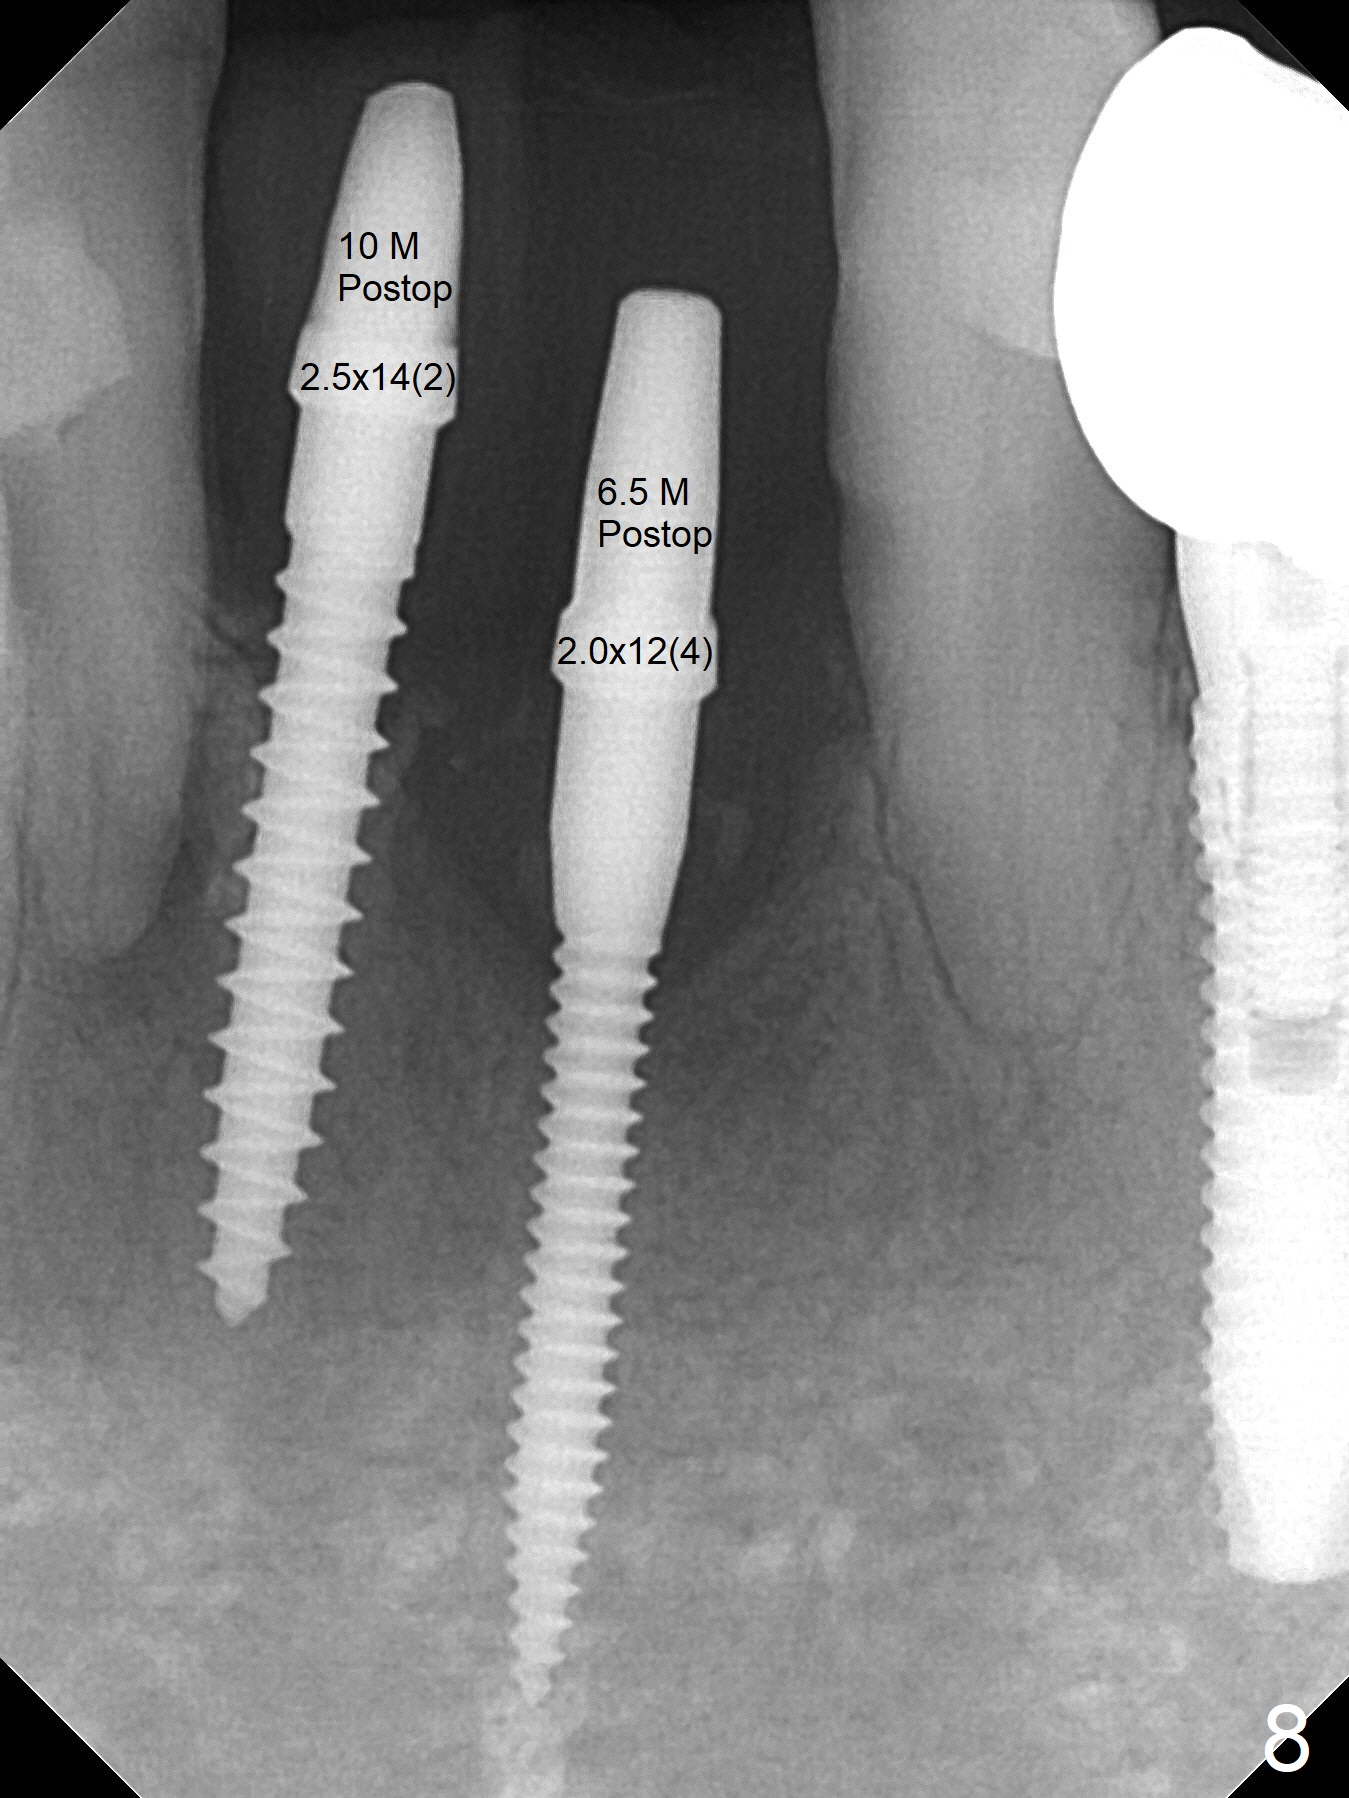

Two and a half months after loss of a 2 mm 1-piece approximately at #23 (Fig.1,2), it appears that the site of #24 (Fig.3 line) is more appropriate because the bone is higher. After removal of the pointed ridge top, osteotomy is initiated with 1.2 mm drill, followed by 1.5 mm one (Fig.4,5). When the 1.5 mm drill is removed, the new osteotomy (Fig.6 *) is mesial to the old one (^). Since the ridge is narrow (Fig.5,6), a 2x14(4) mm 1-piece implant is placed with GBR (Fig.7). Due to overprep, the torque is 20 Ncm. No immediate provisional is fabricated. Instead periodontal dressing is applied around these 2 implants. Two separate provisionals are fabricated when the wound heals. The one at #24 does not stay. The implant at #24 appears to osteointegrate 6.5 months postop (Fig.8). When the crowns are cemented, the margin is supragingival (Fig.9,10). Water Pik is recommended.